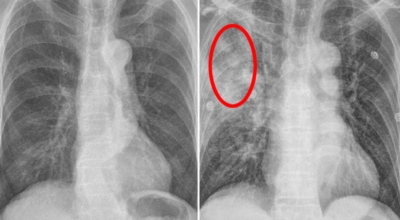

폐암 원인

폐암의 가장 큰 원인이며, 폐암 환자의 80-90%가 흡연에서 비롯될 수 있다고 할 수 있어요. 흡연을 자주 할 시 폐암 발생 위험이 흡연을 하지 않은 사람보다 13배가 증가를 할 수가 있고, 간접흡연 역시 1.5배나 폐암 걸릴 확률이 있어 흡연은 폐암 그 자체라고 생각하시면 될 것 같아요.

가족력으로 폐암에 걸릴 수가 있어요. 친척 포함 가족력 역시 폐암을 무시할 수가 없는데 가족 중 폐암을 가지고 있는 사람이 있을 경우 2~3배 발병률이 높는 것으로 알려져 있어요. 마지막은 생활환경이지요. 흡연 외에도 가스, 미세먼지, 암 유발 물질 노출, 대기오염 과 같은 생활환경에 따라 폐암이 발생할 수 있어요.